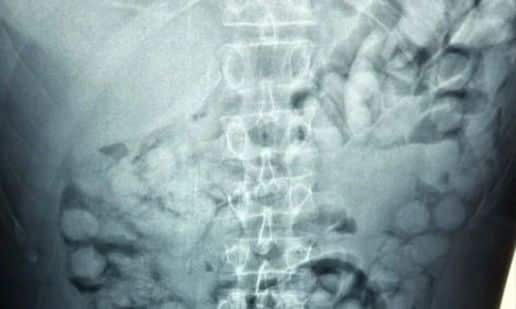

Συνελήφθη ένας άνδρας, από τη Βραζιλία, σήμερα το πρωί στο αεροδρόμιο «Ελευθέριος Βενιζέλος», κατηγορούμενος ότι είχε καταπιεί σημαντική ποσότητα κοκαΐνης.

Σύμφωνα με την Ελληνική Αστυνομία, ο άνδρας έφτασε στην Αθήνα, μέσω Παρισιού και στον έλεγχο που διενεργήθηκε, διαπιστώθηκε ότι είχε καταπιεί περίπου 100 μικρά πακέτα της ναρκωτικής ουσίας.